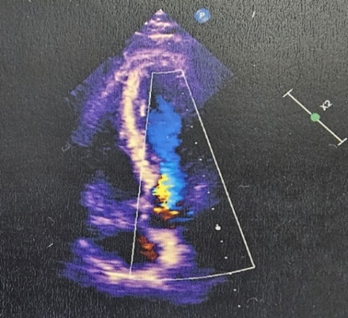

Echocardiogram showed basal inferior-infer septum, mid basal posterolateral wall moderately with mild mid anteroseptal - anterior wall hypokinesia, mild to moderate LV systolic dysfunction (EF:40-45%), mitral regurgitation, normal RV function.

Figure 3: Echocardiography showing mild regurgitation with hypokinesia with mild to moderate LV dysfunction.